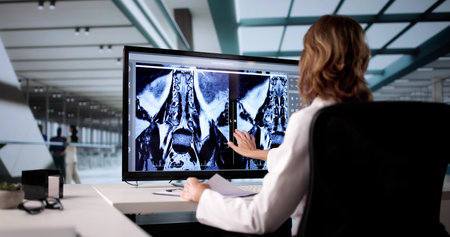

veterinarian doctor with MRI computer control